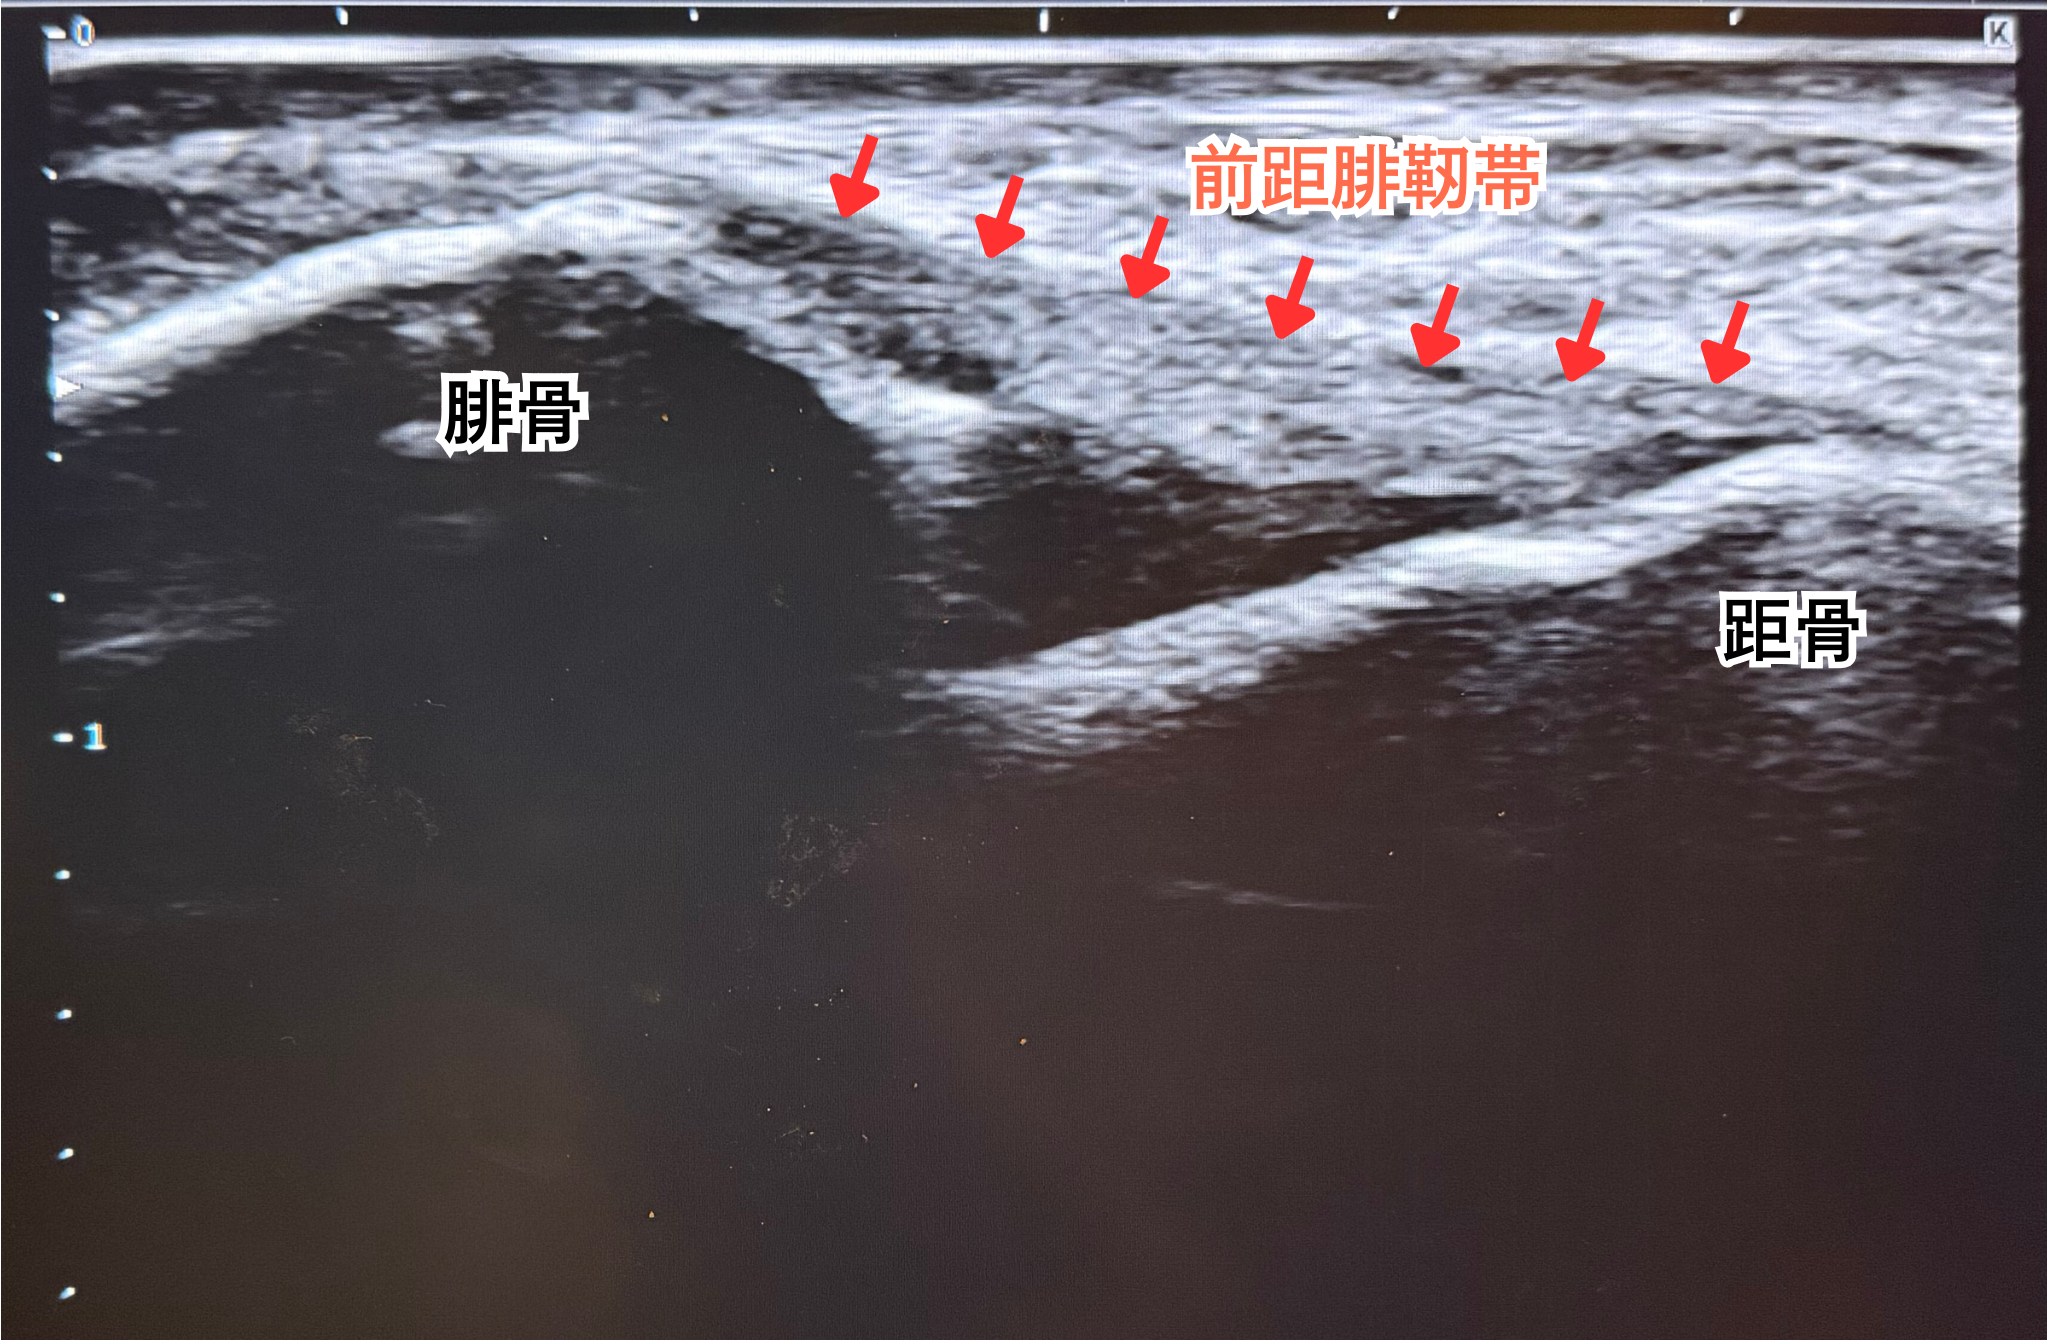

当院では、捻挫の評価に超音波エコーを導入しています。

✅どこの靭帯を損傷しているのか

✅骨との付着部が剝がれていないか など